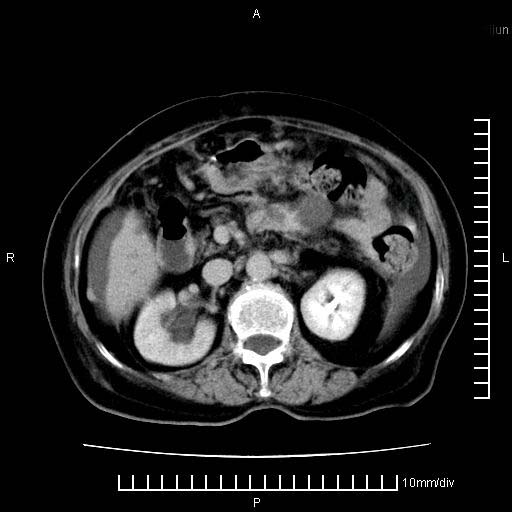

标题: CT28280:腹部增强:女性,80岁

上腹疼痛月余,外院核磁诊断胰腺癌。现临床示右下腹可明显触及包块,可片子上怎么没有看到?

4。右肾盂囊肿。

右肾盂囊肿。

3、右肾盂囊肿。

1)考虑胰腺癌并胰腺假性囊肿形成。2)肝内低密度灶,不排除转移。3)右肾盂积水。4)腹水。5)右侧胸腔积液并右肺下叶部分膨胀不全。

考虑胰腺ca伴腹膜腔转移、肝左叶转移、右肾积水。右胸腔积液。